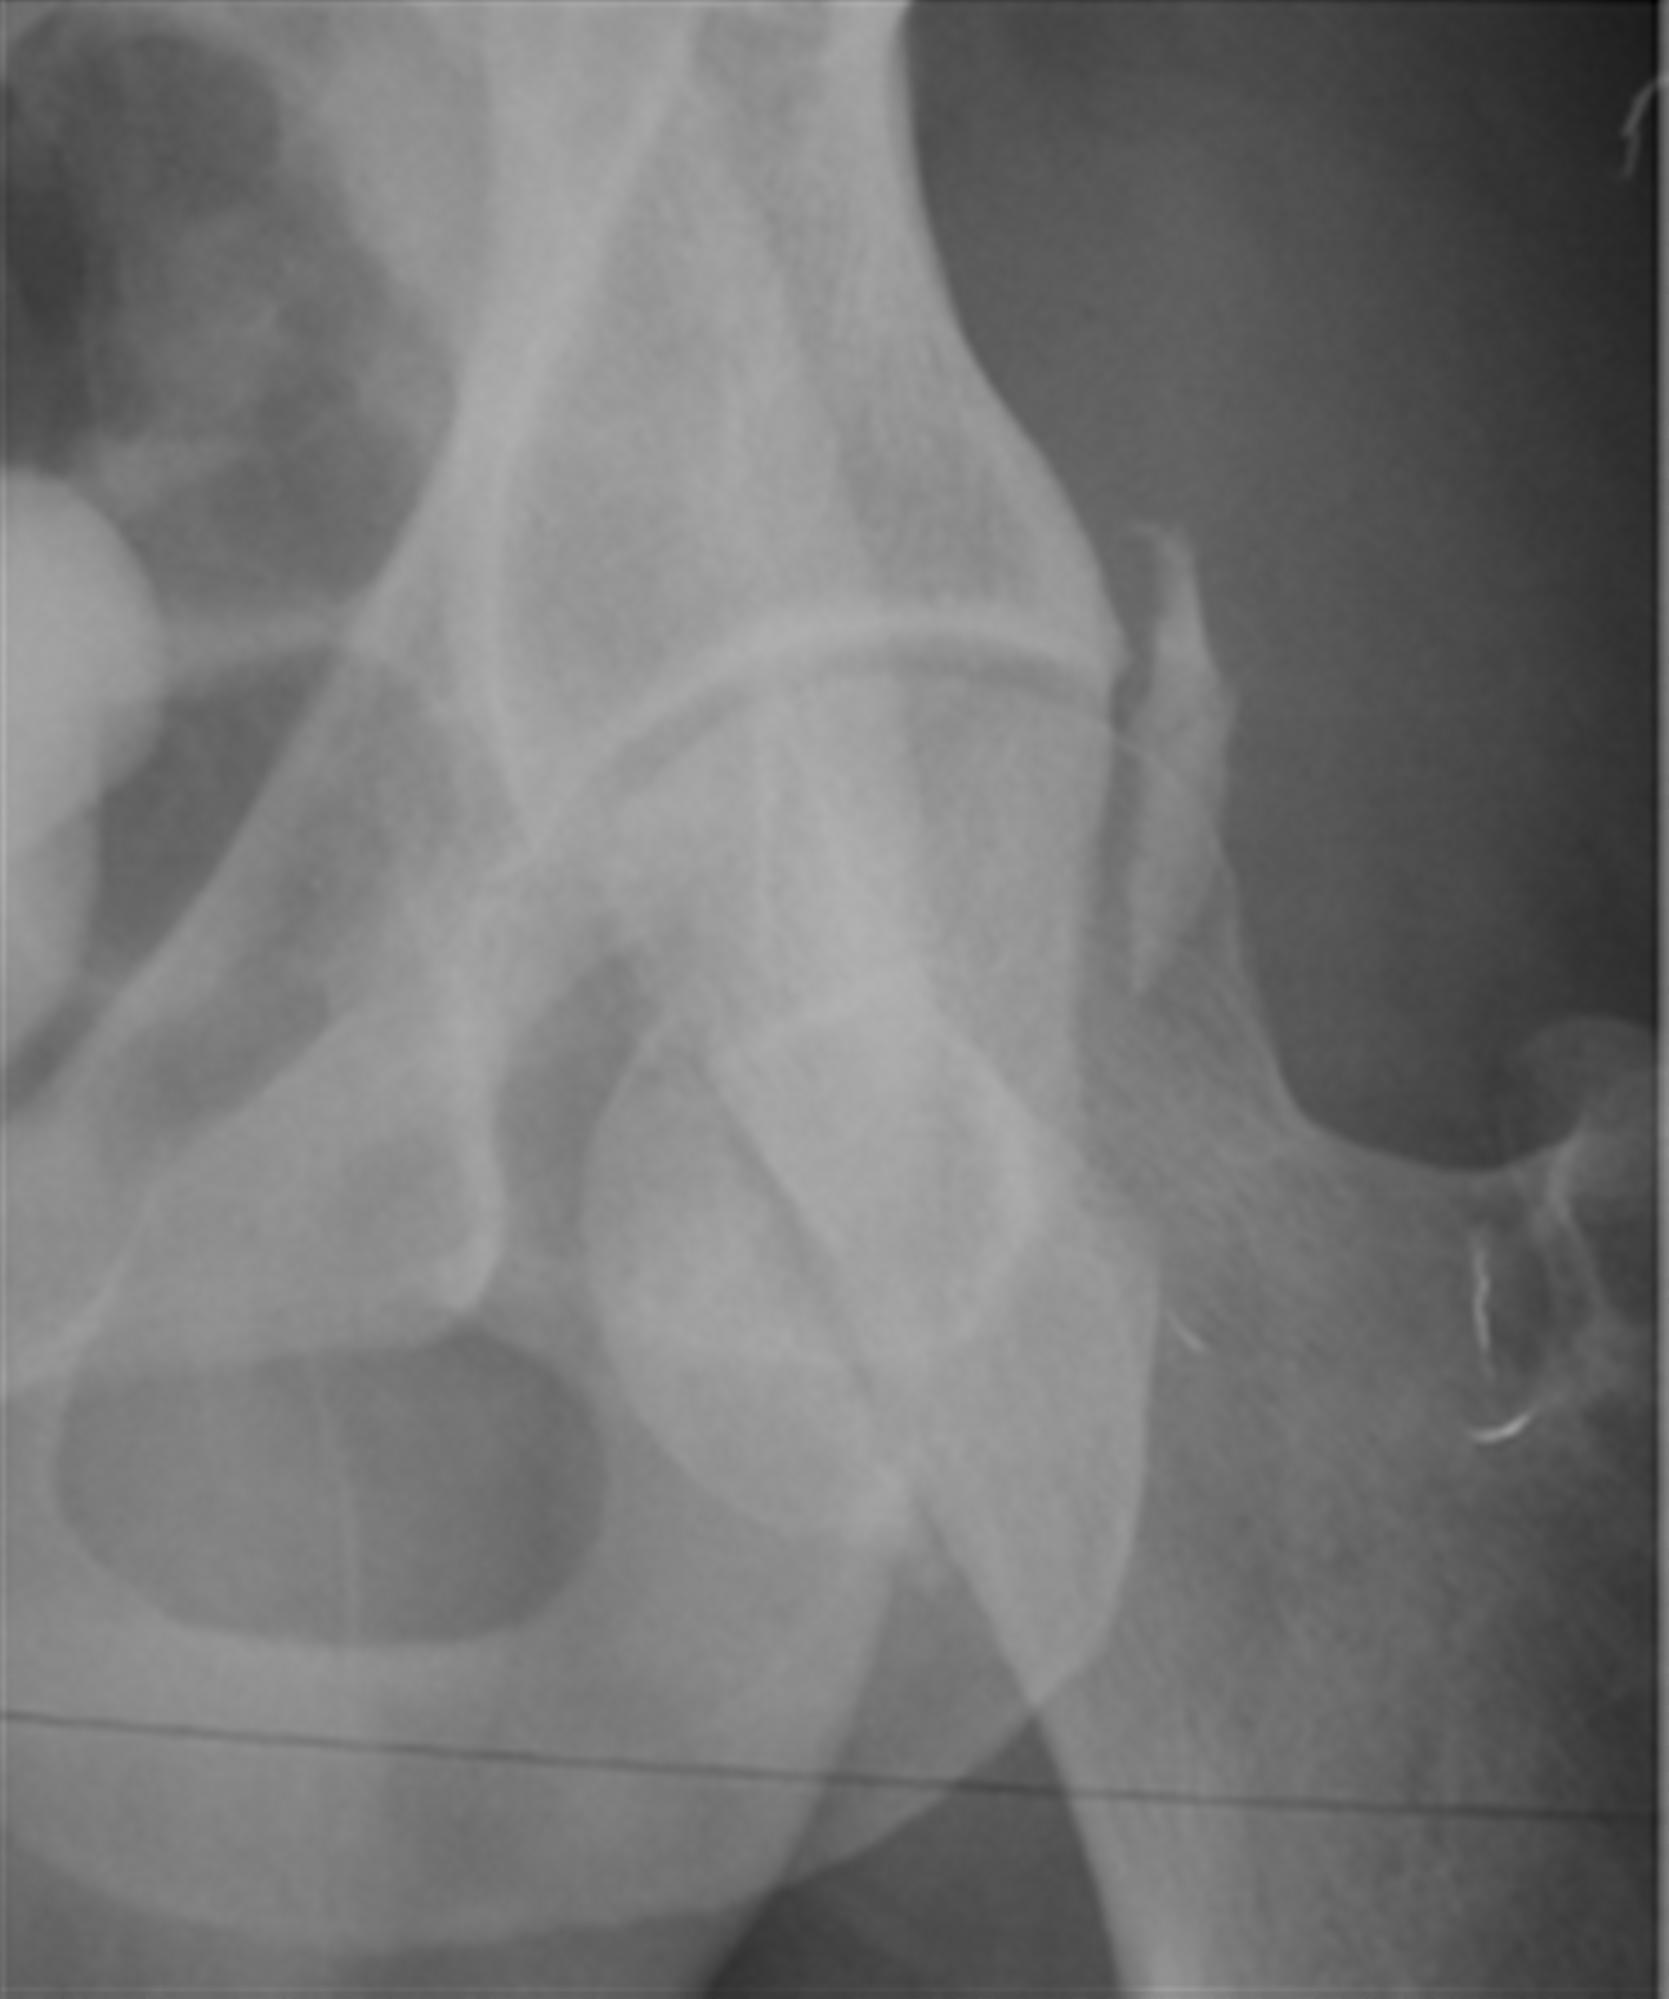

Talus Fracture (other than neck)